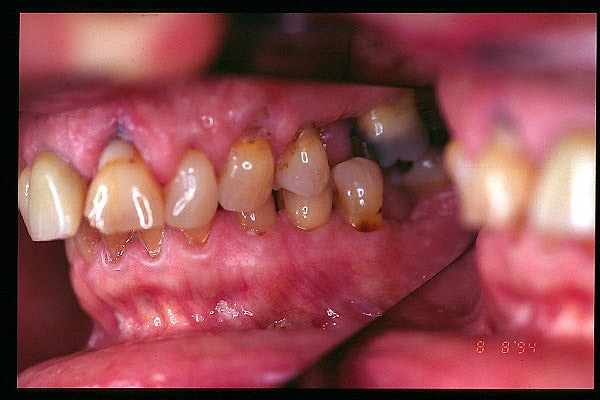

CM Caries, patología periodontal, desgaste.